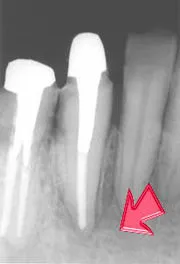

治療後の状態

こうなってしまっては、通常の「削る、詰める」といった治療方法で治すことはできません。そこで行うのが根管治療です。専用の極細い器具を使用し、歯の根っこの管の中をきれいにお掃除していきます。

歯の根っこの中にある管は、とても細く、さらに枝分かれしたり曲がったりしているため、完全にきれいにするのはかなり難易度が高いというのが正直なところです。

そのため、治療は何度か繰り返すのが通常で、患者さまにも根気良く通っていただく必要があります。とは言え、歯を残すための最後の治療ですので、諦めずに一緒に頑張っていきましょう。